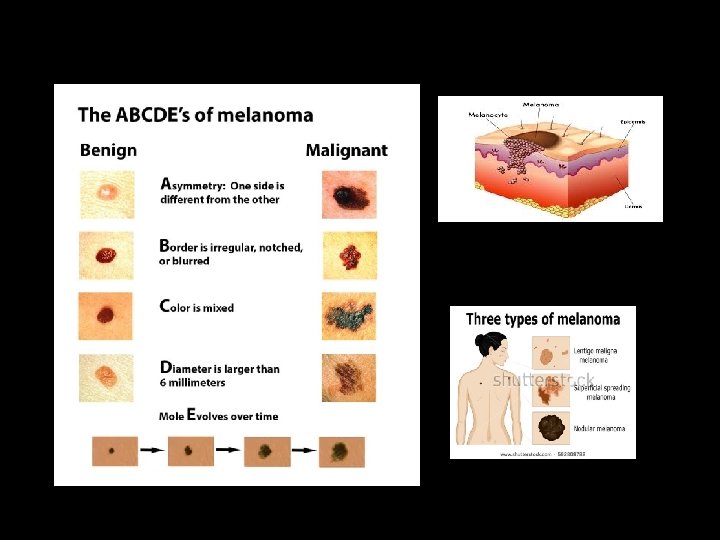

ORAL MELANOMA • Melanoma malignant tumor of nevus cells • Have a nodular component • Slightly more in males • 4 presentations – pigmented macule – pigmented nodule – large pigmented exophytic lesion – Amelanotic variety • Color mucosal pink – brown – blue – black • May ulcerate but no rolled out borders

• Rate of growth slow • Vertical phase rapid • Usually painless • Rapid infiltration fixed to underlying tissues • Spread lymphatic & hematogenous routes • Many develop from nevi

ORAL MELANOMA A – asymmetry C – color variation B – border irregularity D – diameter > 6 mm D/D: • Oral melanotic macule • Amalgam tattoo • Nevus • Focal hemosiderin deposit